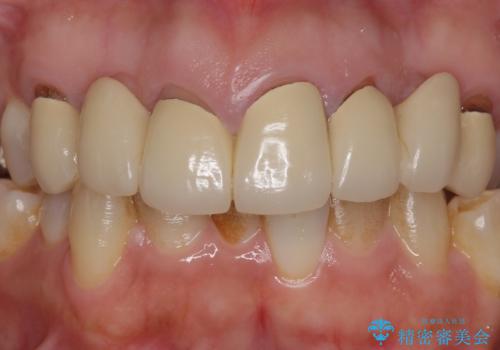

- 昔治療した前歯の被せ物の見た目を改善したいといらっしゃった方の症例です。

左上4番目の歯から右上3番目の歯まで計7歯のクラウンを除去し、オールセラミッククラウンによる補綴を行いました。

- オールセラミッククラウン…¥100,000×7、仮歯…¥10,000×7、ファイバーコア…¥20,000×5費用は治療当時の料金となります